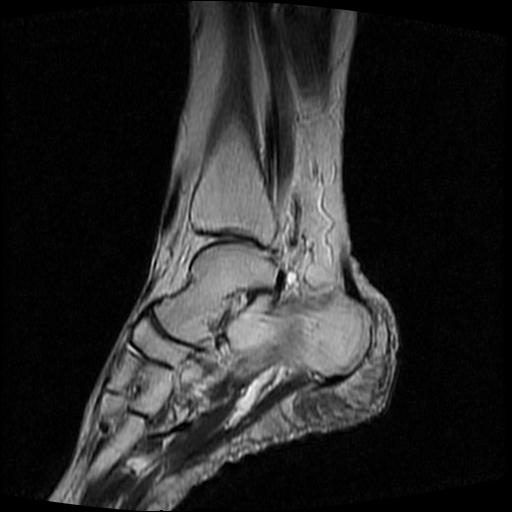

标题: MRI0968:女性,70岁,跟骨信号异常 [打印本页]

标题: MRI0968:女性,70岁,跟骨信号异常

女性,70岁,右侧跟骨疼痛2个月,负重时加剧,不负重时不疼。

胫骨下段,跟骨、距骨可见斑片状异常信号区;考虑:转移瘤

跟骨长t1长t2信号异常,边缘模糊(肿瘤一般边界清楚,故肿瘤不考虑),压脂像呈高信号--骨髓水肿(炎症?)。